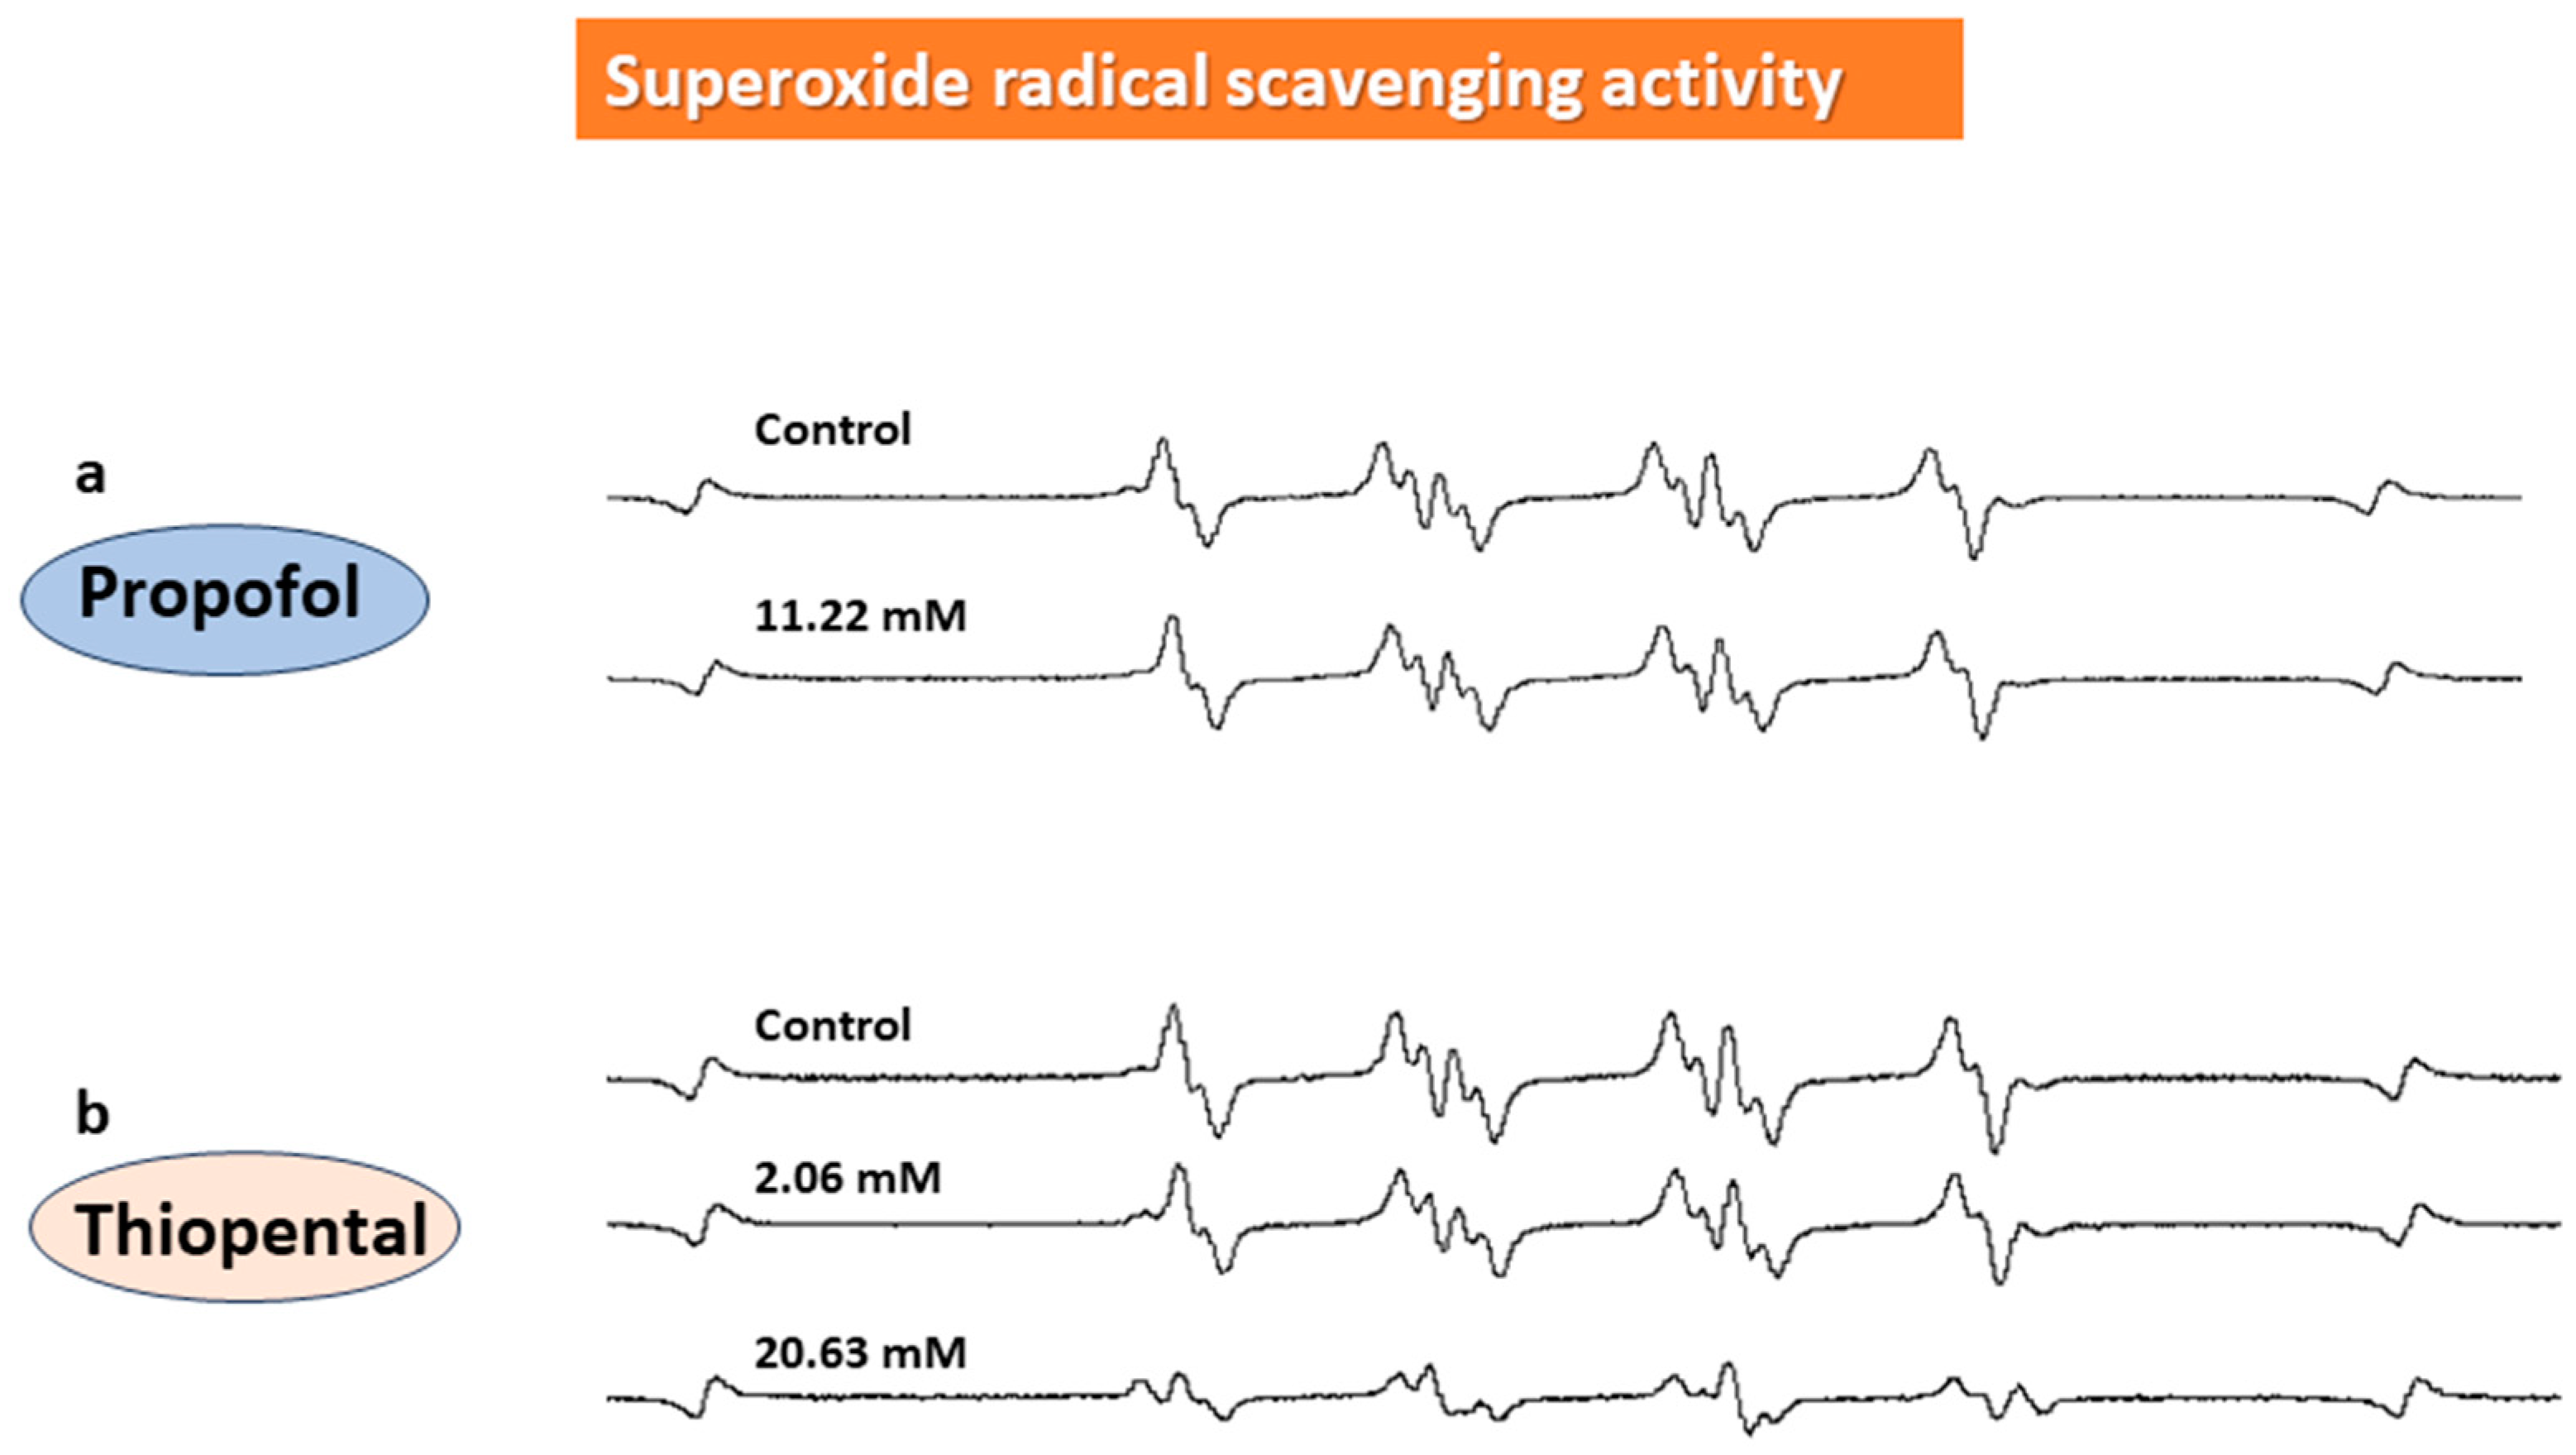

2.2. In Vitro ESR Method

3. Results